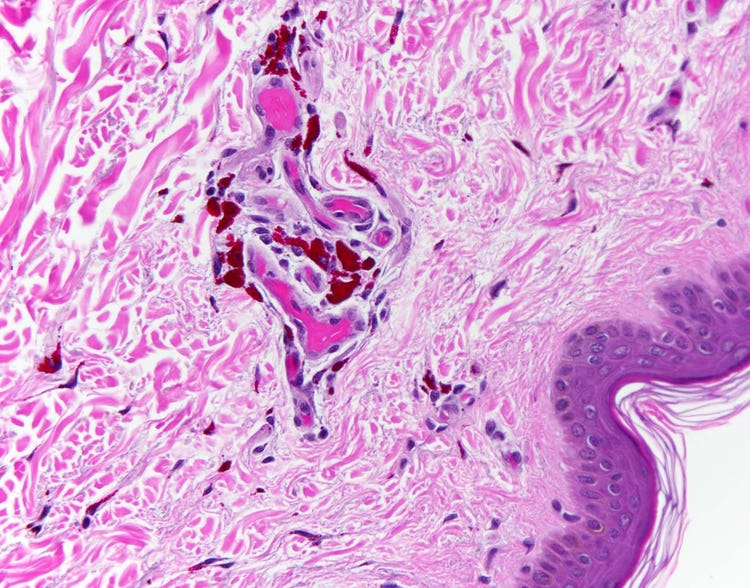

Pigmento rojo de tatuaje visto bajo el microscopio

Sección de piel humana tatuada. Los gránulos individuales de pigmento pueden apreciarse en la dermis, la capa profunda de la piel, en gran magnificación. Otros colores, identificables con el microscopio, son los gránulos de pigmento negro, azul y dorado. Captura llevada a cabo con un microscopio Olympus BX43 dotado de una cámara DP26. Imagen por cortesía de Marianne Hamel.